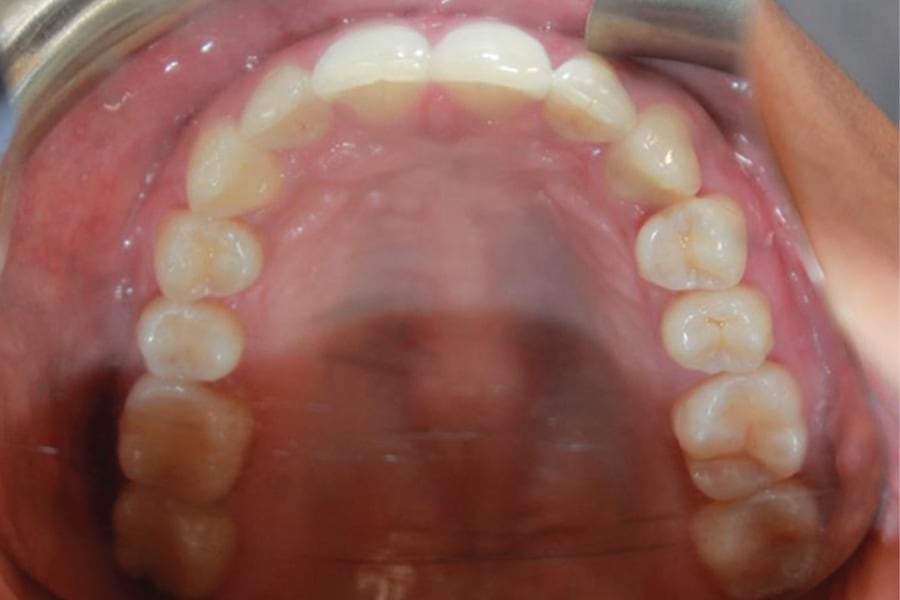

A 35-year-old woman presented with concerns of crowding, bruxism, and bite misalignment, which were associated with a class II malocclusion that would require a combination treatment of expansion, distalization, and molar derotation. ClearCorrect® aligner therapy (Straumann, clearcorrect.com) was selected as the primary modality, as the patient requested a non-invasive, esthetic treatment. The treatment plan was designed to be completed within 6 months of active aligner therapy. Class II elastics were prescribed, and the ClearCorrect FLEX case plan was chosen to allow for refinements, as needed. After comprehensive digital records were taken, the first set of aligners was delivered, engagers were bonded, and the patient was instructed to wear aligners on a 14-day cycle with full-time class II elastic wear. To enhance efficiency, more engagers were placed, including posterior attachments, to maximize control over molar distalization and anchorage. Interproximal reduction of 0.3 mm was performed in a few contacts at the initial appointment to facilitate space closure and alignment. Due to the complexity of the correction and the patient’s history of bruxism, a lower 3-3 bonded retainer was placed, and retainers were fabricated for both arches. The patient expressed a high level of satisfaction with the ClearCorrect aligner therapy, noting the comfort and esthetics of the aligners and the ability to achieve a fully corrected class II occlusion in just 6 months of treatment.